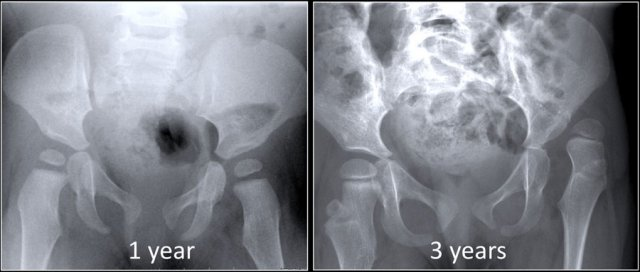

Results from the loss of blood supply - the femoral head is the most frequent site of it - often necessary to obtain two radiographs in patients with this condition. The first is taken with normal density, whereas the second is made with increased kVp to allow for adequate penetration of the more opaque ischemic bone.

Ischemic Necrosis

Associated with ischemic necrosis of bone. Ischemia results from poor blood supply to the bone. Affects the epiphyses and may be mistaken for tuberculosis of the skeletal system. Tends to occur in males between the ages of 5 to 10 years and often follows injury to the affected hip. Radiographically the bone in the center of the epiphysis is fragmented and the head of the femur is flattened.

Legg-Perthes Disease